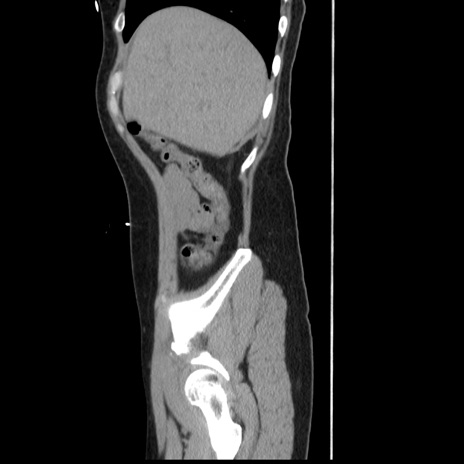

横断像